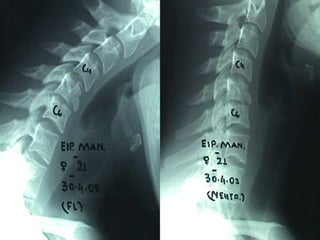

–RRaaddiiooggrraapphhiicc

XX--rraayyss

–AAPP,, LLaatteerraall,, sswwiimmmmeerrss

vviieeww

–EEvvaalluuaattee ppoosstteerriioorr

ssttrruuccttuurreess

–IInnssttaabbiilliittyy ppaatttteerrnnss